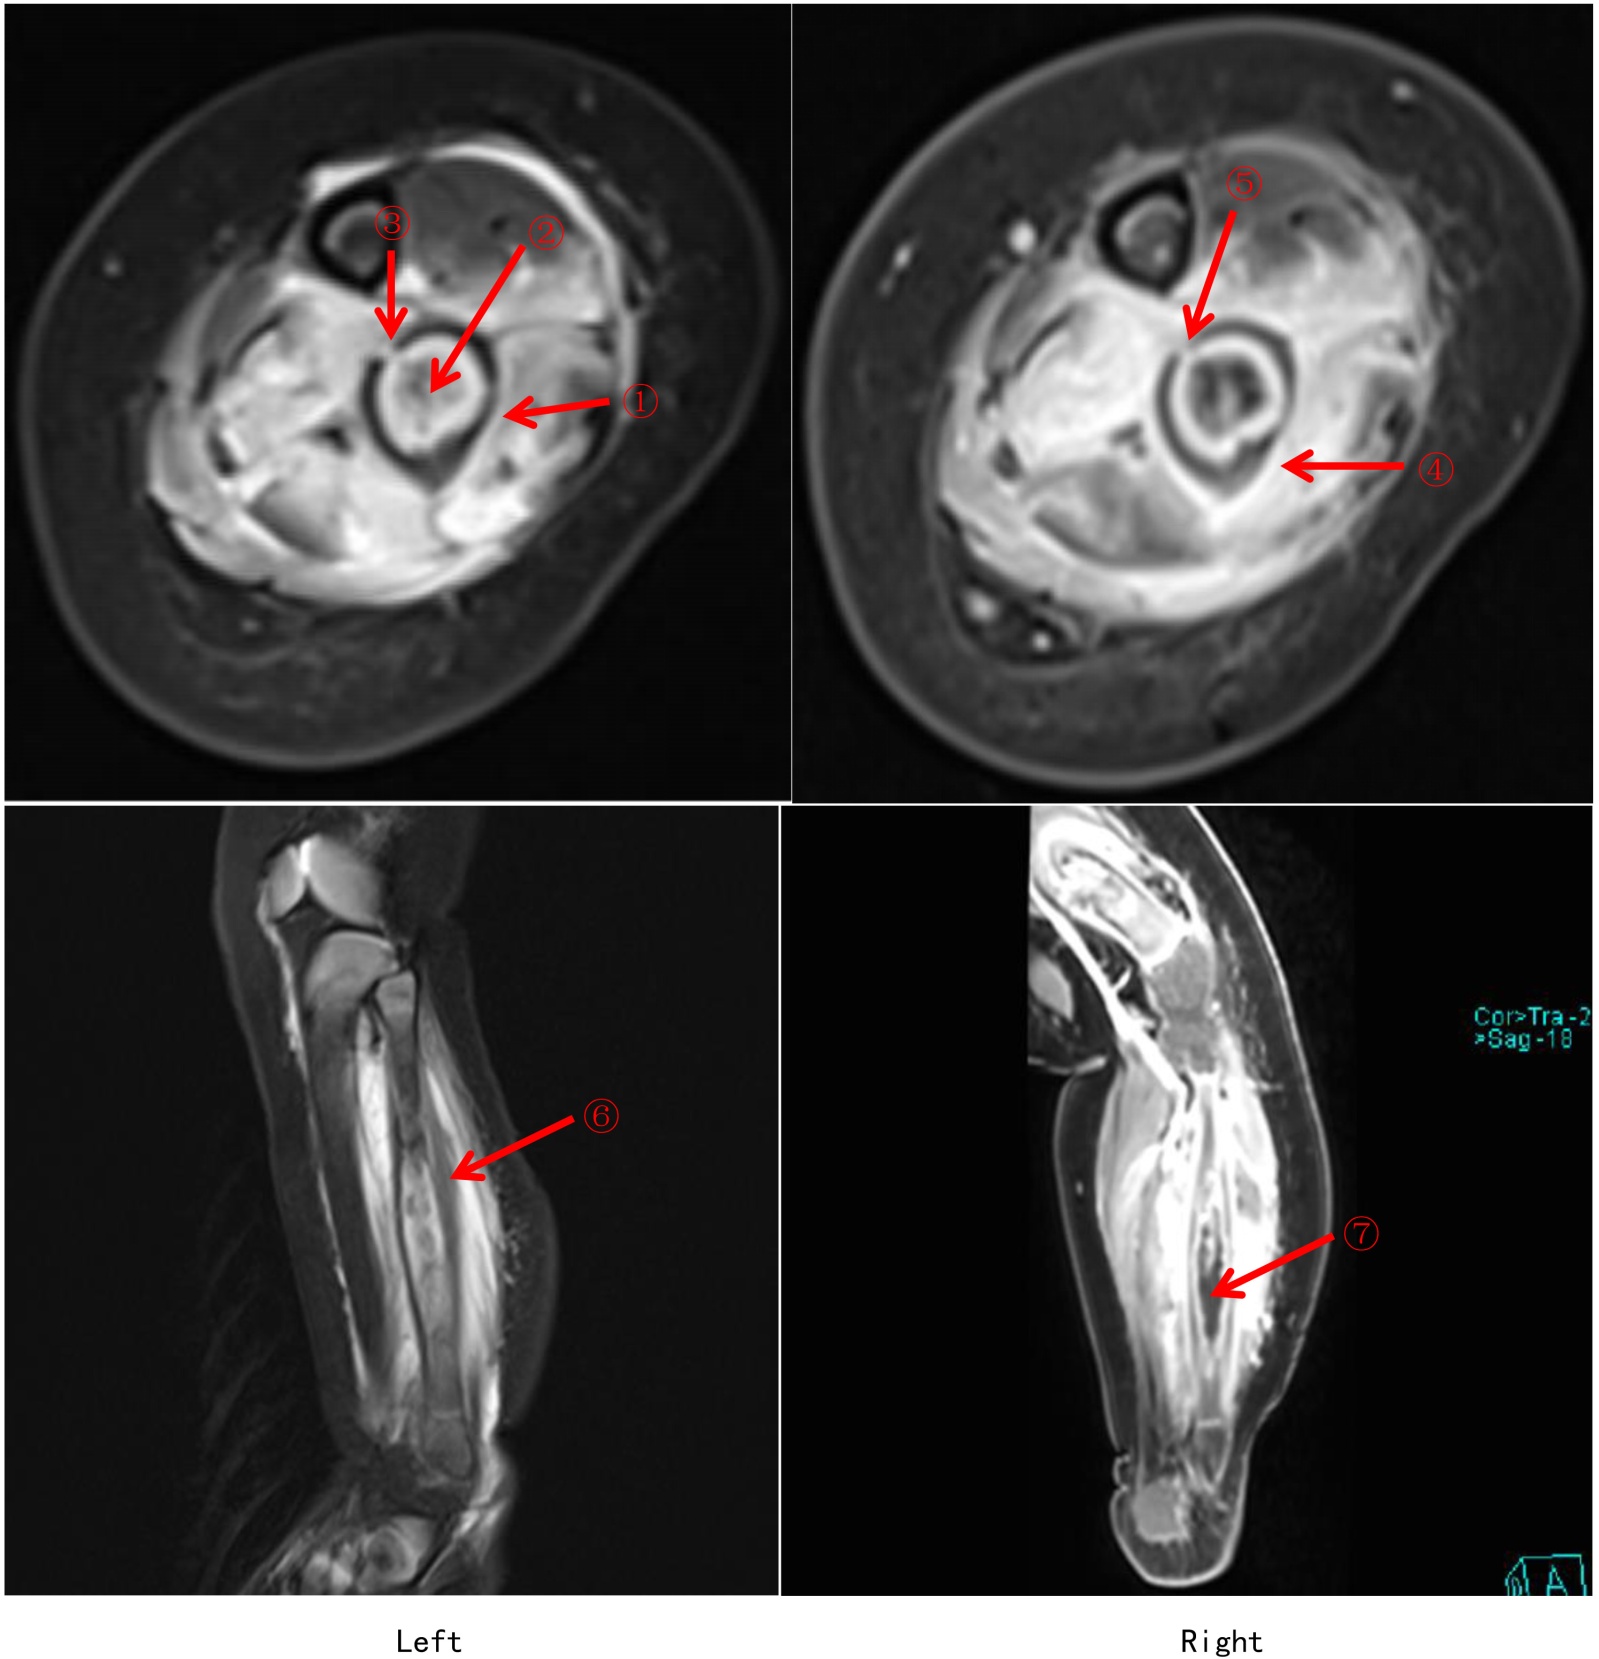

(5) 入院后完善相关检查:2025-09-10,CRP+血常规:C反应蛋白21.43 (mg/L)↑,白细胞计数13.24 (×10^9/L),中性粒细胞计数4.62 (×10^9/L),淋巴细胞计数7.39 (×10^9/L),红细胞计数3.96 (×10^12/L),血红蛋白95 (g/L)↓,血小板计数546 (×10^9/L);2025-09-22,CRP+血常规:C反应蛋白43.80 (mg/L)↑,白细胞计数11.24 (×10^9/L),中性粒细胞计数4.17 (×10^9/L),淋巴细胞计数6.23 (×10^9/L),红细胞计数3.56 (×10^12/L),血红蛋白82 (g/L)↓,血小板计数627 (×10^9/L)↑;2025-09-17,细胞因子:白介素6 29.66 (pg/ml)↑,白介素102.62 (pg/ml)↑,干扰素γ 23.76 (pg/ml)↑;2025-09-23,红细胞沉降率76 (mm/h)↑;大小便常规、降钙素原无异常;肝肾功能、电解质、血糖、血脂、心肌酶谱、凝血功能、免疫功能、风湿全套、狼疮全套大致正常,贫血三项:铁蛋白244.06 (ng/mL)↑;病原学检查:尿培养、痰涂片、输血前、血培养、未见异常。2025-09-16,病原体高通量测序基因检测:人类疱疹病毒5型(CMV)序列数(1993)相对丰度(86.5%);2025-09-10上呼吸道六项病原核酸检测:入院时阴性,住院期间(2025-09-16)呼吸道合胞病毒,阳性(+)↑。影像学检查:2025-09-12,左胫腓骨磁共振(如图2):左侧腓骨髓腔长段囊腔样扩展,髓腔内可见异常强化,骨皮质菲薄,骨膜层状反应性环状增生增厚,骨质破坏不明显,周围软组织明显肿胀、无脓肿及坏死灶形成。2025-09-17,胸部正位片(如图3) + 右股骨正位片和右胫腓骨正位片(如图4):右肩胛骨重叠区、右股骨远端、右胫骨上段低密度影,性质待定,建议进一步检查。2025-09-23,颌面部磁共振(如图5):下颌骨左侧部骨皮质明显不规则增厚,边缘模糊、毛糙,呈T1W1、T2W1低信号,临近软组织肿胀呈明显T2W1高信号。腹部超声未见异常。病理检查:2025-09-15,免疫组化:(左侧小腿软组织)送检肌组织,肌间可见少许淋巴细胞、嗜酸性粒细胞及中性粒细胞浸润,多切片未见恶性证据,请结合临床综合考虑。免疫组化IHC: A01: CK (pan) (−),CD207 (−),CD20 (少量B细胞+),CD1a (−),S-100 (−),Ki67 (+, 约10%),CD3 (少量T细胞+),TdT (−),CD34 (血管+),MPO (少量+),SMA (−)。原位杂交:EBER (−)。基因检查:GATA2 (chr3: 128200145)杂合变异;EXT2 (chr11: 44219362)杂合变异。

Figure 2. MRI Findings of the left tibia and fibula (Left: pre-contrast; Right: post-contrast)

2. 左侧胫腓骨磁共振(左图:平扫,右图:增强)

左侧腓骨髓腔长段囊腔样扩张,髓腔内可见异常强化、无脓肿形成,骨皮质菲薄,骨膜层状反应性环状增生增厚,骨质破坏不明显,周围软组织明显肿胀、无脓肿及坏死灶形成。①、④、⑥为骨膜层状反应性环状增生增厚;②、⑦为扩张的骨髓腔,腔内未见脓肿;③、⑤可见哈弗氏管的骨皮质扩大,周围未见脓肿。